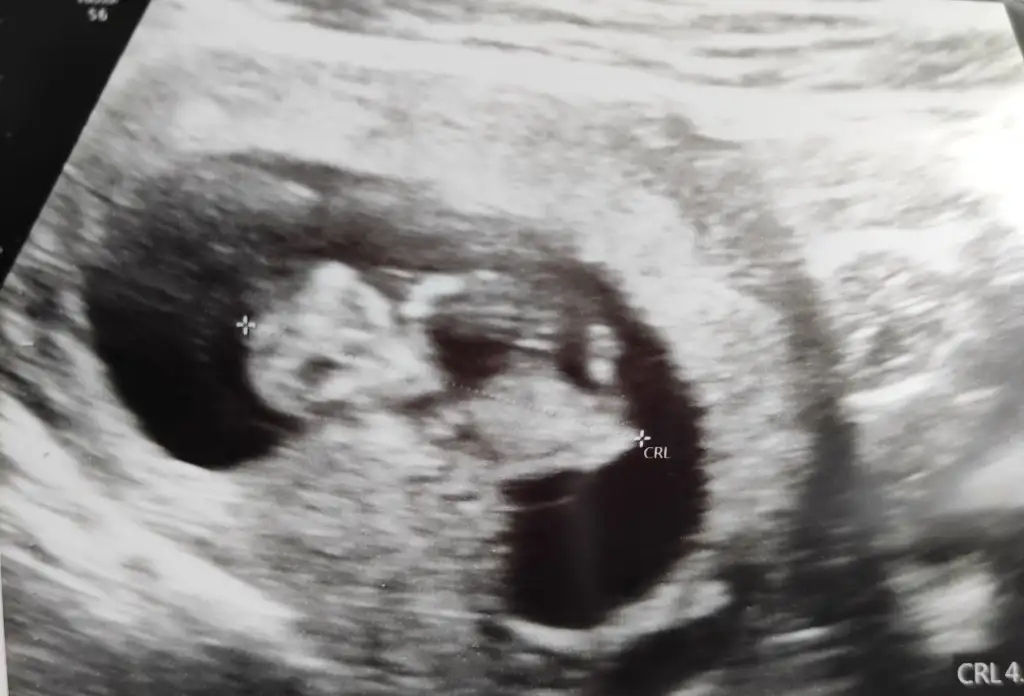

Merhaba 11 haftalık hamileyim bende bir aksilik olmazsa Aralık sonu ile 13 Ocak'a kadar doğum bekliyorum :) Biz cinsiyetini hala sormadık ve öğrenmedik bir süre daha öğrenmeyi düşünmüyorum, eskiden hep kız çocuk isterdim ama nedense oğlum olduğunu hissediyorum,

İlk testte betahcg 10.000 üzeri çıktı, şuan en çok zorlandığım şey sinüzit ağrıları ile baş edemiyorum ağrı kesici içmemek için çıldırıyorum resmen günlük enerjimi çok etkiliyor ve beslenmeme de dikkat edemiyorum sinüzit ağrılarım olduğu zaman